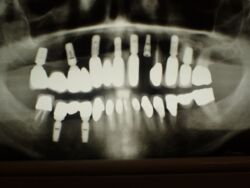

Das Problem dieses Patienten besteht darin, dass der Patient zum einen anlagebedingt, zum anderen parodontitisbedingt, unwahrscheinlich lange klinische Zahnkronen besitzt. Das vermag man auch als Laie an dem nebenstehenden OPG zu erkennen. Eine derartige Situation ist nicht der Durchschnittspatient, kommt aber im fortgeschrittenen Alter schon regelmäßig vor.